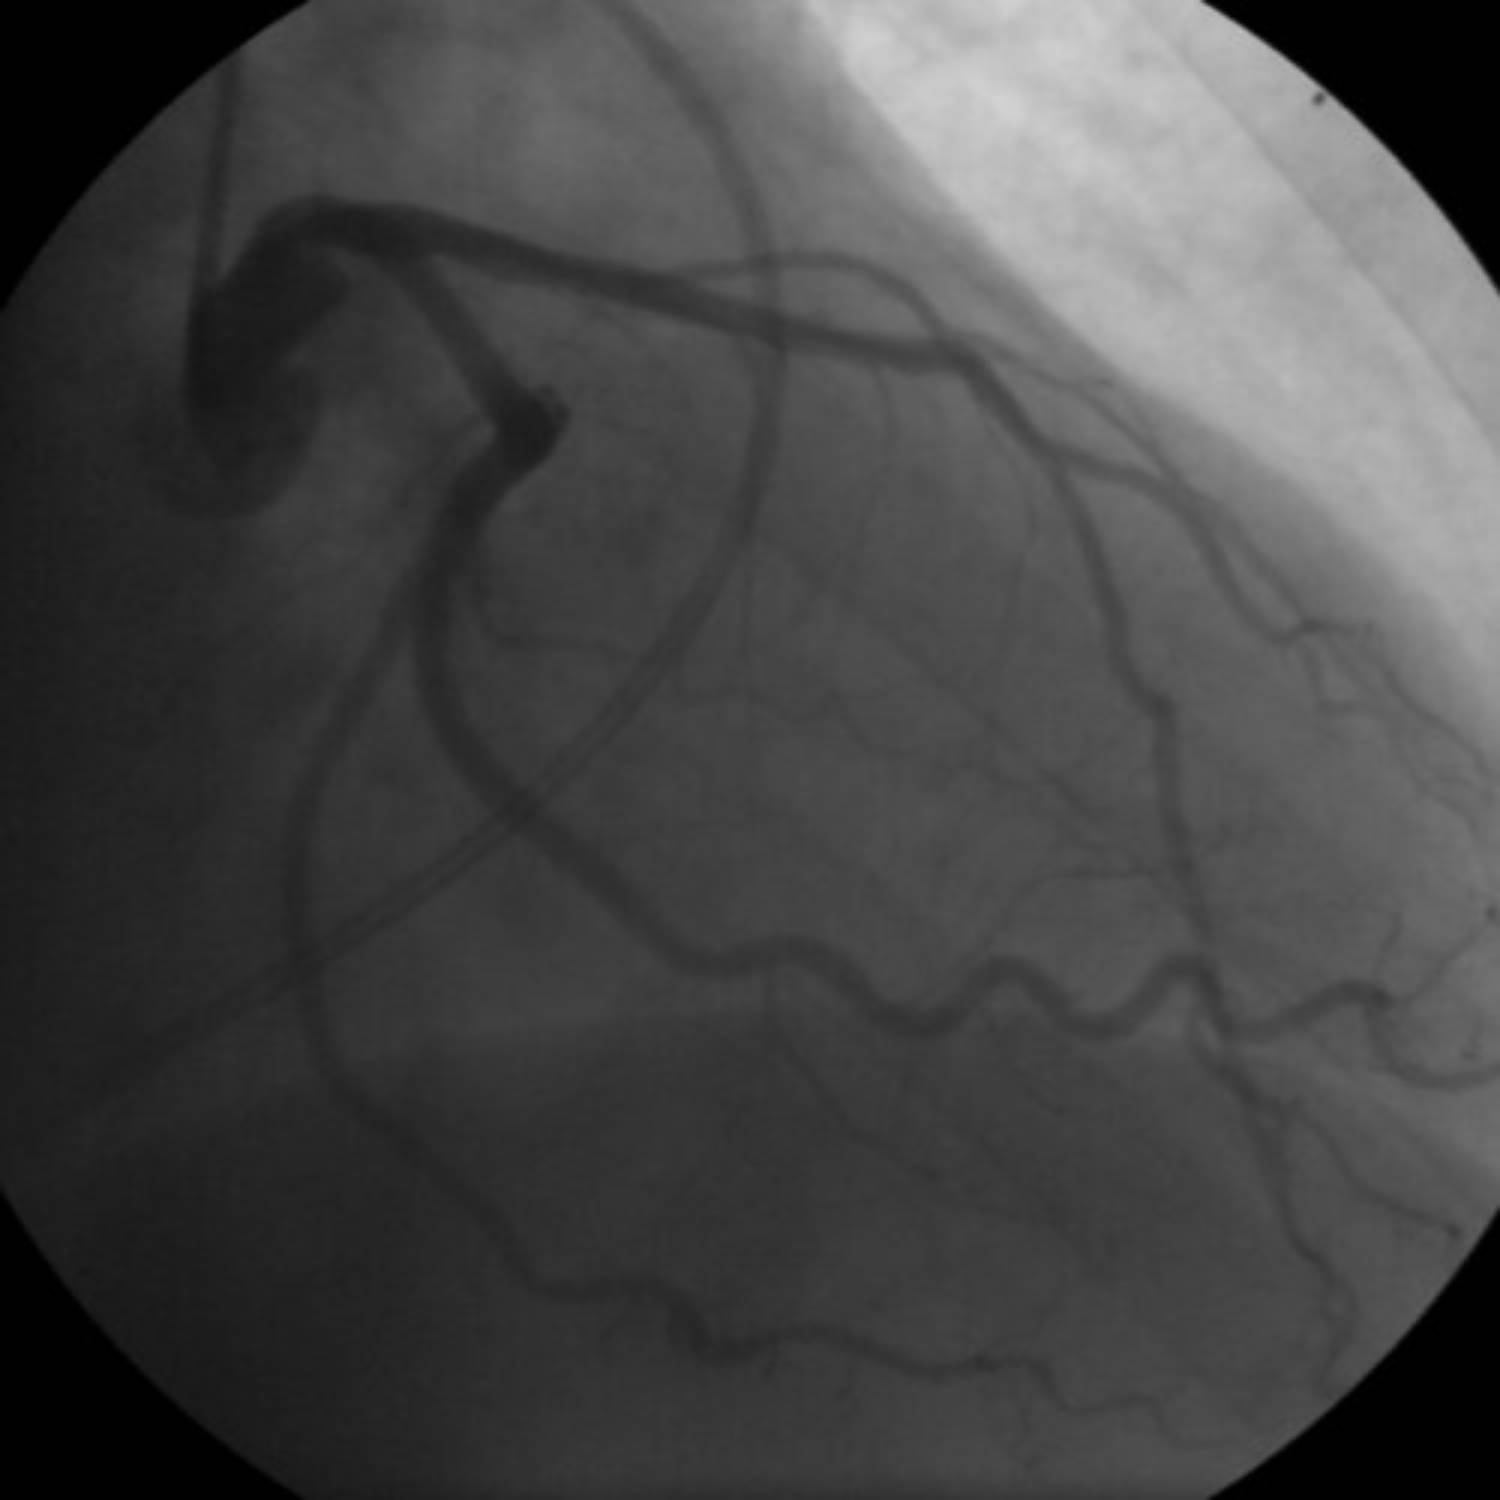

This image presents a coronary angiogram of a female patient, offering a crucial diagnostic perspective on her cardiac vasculature. Coronary angiography is an essential medical procedure used to visualize the coronary arteries, the blood vessels responsible for supplying oxygen and nutrients to the heart muscle. By using a contrast agent and X-rays, this technique allows medical professionals to detect potential blockages or narrowings that could indicate coronary artery disease (CAD) or other significant cardiac issues. This detailed view is vital for accurate diagnosis and guiding personalized treatment plans.

Coronary angiography is a sophisticated imaging technique that plays a pivotal role in the diagnosis and management of heart conditions, particularly coronary artery disease. This procedure involves the injection of a special dye into the coronary arteries, which then become visible under X-ray imaging. The resulting angiograms, such as the one displayed, enable cardiologists to assess the patency of the arteries, identify stenoses (narrowings), and evaluate the overall blood flow to the heart muscle. While the fundamental principles of angiography remain consistent, there can be subtle differences in presentation and clinical implications between genders.

Coronary artery disease (CAD) develops when plaque, made up of cholesterol, fatty substances, and other cellular material, builds up inside these arteries. This process, known as atherosclerosis, causes the arteries to narrow and harden, restricting blood flow to the heart muscle. When the heart muscle doesn’t receive enough blood, it experiences ischemia, which can lead to symptoms like angina or, in severe cases, a heart attack. Females can sometimes present with what is termed “non-obstructive CAD” or coronary microvascular dysfunction, where smaller arteries or capillaries are affected, which may not always be clearly visible on standard angiograms but can still cause significant symptoms. The image allows for direct visualization of these major vessels to identify gross obstructions.

During a coronary angiogram, a catheter is carefully guided to the openings of the coronary arteries. A contrast dye is then injected, making the arteries visible on X-ray screens. The rapid sequence of X-ray images, or fluoroscopy, captures the flow of the dye through the arteries, allowing the cardiologist to observe any areas where the blood flow is restricted. These restrictions, or stenoses, are often indicative of atherosclerotic plaques. The severity of these narrowings is typically measured as a percentage of the vessel’s diameter, which directly impacts treatment decisions.

The diagnostic value of an angiogram lies in its ability to precisely locate and quantify blockages. For instance, a total occlusion signifies a complete blockage, while a partial blockage may still significantly impede blood flow. In addition to identifying stenoses, an angiogram can also reveal the presence of collateral vessels—smaller blood vessels that can develop over time to bypass a blocked artery, offering some compensatory blood flow. This detailed information helps the cardiology team understand the extent of the disease and plan the most appropriate intervention, whether it’s medication adjustment, percutaneous coronary intervention (PCI) with stenting, or coronary artery bypass grafting (CABG).